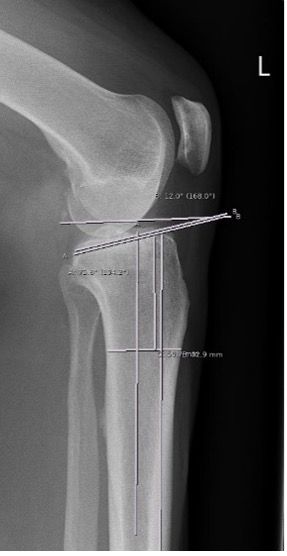

Preoperative deformity analysis in the frontal plane according to Paley [13]

Determination of weight bearing line (Mikulicz line), MPTA (medial proximal tibia angle), mLDFA (mechanical lateral distal femoral angle) and the mechanical varus angle are the 4 key parameters of analysis in the frontal plane (Fig. 1a). The joint line obliquity (JLO) and joint line congruence angle (JLCA) are used as extended parameters for the planning of a double level osteotomy (DLO) in varus deformities on the femur and the tibia as well as the bony correction angle in any varus thrust (Fig. 1b).

With a medial open-wedge correction of the tibia, the MPTA angle should be no more than 94° after the correction, because otherwise the joint line obliquity (JLO) is more than plus 4°, which results in clinically relevant shear forces in the joint and to poorer clinical outcomes.

Cases of major correction (>10°) are almost always due to a combined deformity of femur and tibia. If the deformity is mainly on the femur, the correction must be performed at the femur. In around 10−15% of cases no acceptable joint line obliquity (JLO) can be achieved with only one correction on femur or tibia. In these cases a simultaneous double level osteotomy (DLO) correction on the femur (lateral closing wedge) and tibia (medial open wedge) should be performed [16−17].

Planning with calculation of the correction angle was performed according to Miniaci [18] (Fig. 1e). Planning can be performed either manually or using digital software. It is important when planning the bone correction angle that an abnormal joint line convergence angle (JLCA) (see Fig. 1b) is included in the planning (alpha angle minus JLCA >2°) because otherwise the osteotomy will result in an overcorrection to valgus deformity.